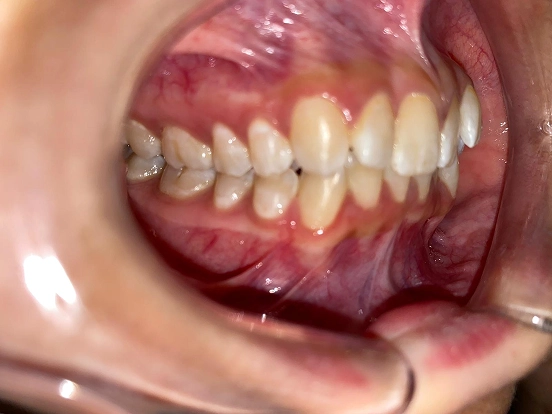

Invisalign CK

This Invisalign case shows how clear aligners can completely transform a smile without the need for metal braces. Over the course of treatment, CK achieved a beautifully aligned smile with improved symmetry and confidence. The results highlight how Invisalign offers both comfort and precision for a stunning new look.